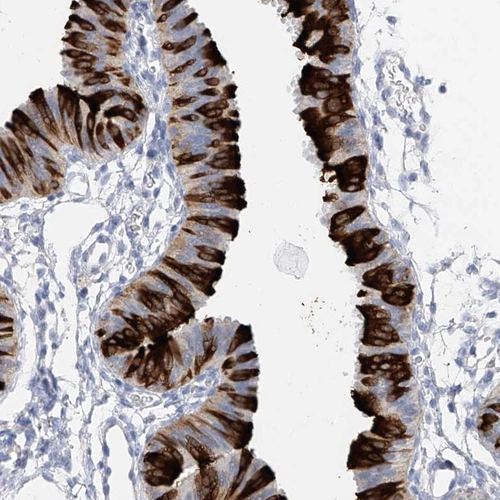

Immunohistochemistry analysis in human fallopian tube and liver tissues using Anti-RSPH4A antibody. Corresponding RSPH4A RNA-seq data are presented for the same tissues.